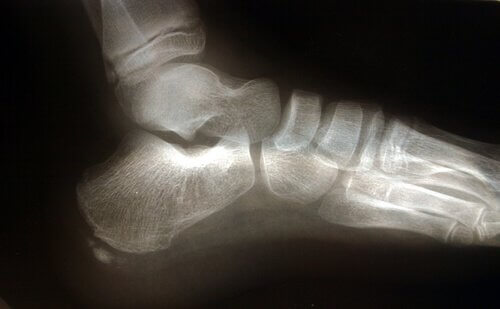

Заболяването плантарен фасцит е възпаление на плантарната фасция на крака, връзка, която свързва костта на петата с близките фаланги и се простира и свива с всяка стъпка, подобно на гумена лента.

Има няколко анатомични структури, които играят роля при всяко претоварване на плантарната фасция.

Ахилесовото сухожилие е връзка, която свързва мускулите на прасеца, известни като прасци, и мускулите на ходилото до костите на петата. Притискането на ахилесовото сухожилие води до увеличаване на натиска върху петата на костта, което води до увеличаване на натиска върху плантарната фасция.

Друг фактор, който трябва да имате предвид в анатомичната структура, е ударът на крака, или с други думи, как кракът се докосва до земята. Плоските крака или крака, които имат тенденция за плоско стъпало разтягат плантарната фасция повече, като по този начин увеличават риска от разкъсване поради допълнителното притискане върху тъканта.

Плантарният фасцит често се свързва с наличието на остеофити, въпреки че не е определящ фактор.